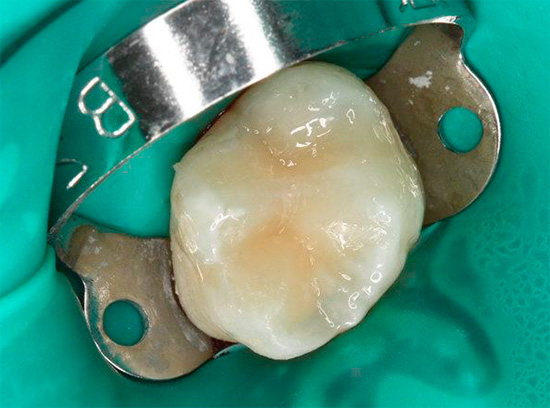

Degli ingredienti attivi nei marcatori di carie, la fucsina acida è il più comunemente usato - un noto colorante sintetico che ha un colore rosso intenso in soluzioni acquose. La foto mostra come le parti cariate del dente sono macchiate con esso: